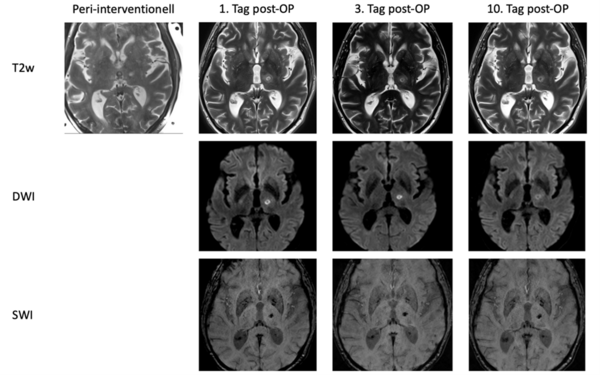

Der Eingriff wird in der Abteilung für Neuroradiologie im MRT (Magnetresonanztomografie) durchgeführt. Nach aufwendigen Vorbereitungen des Gerätes sowie der zugehörigen Systemkomponenten durch die MTR (medizinische Technologen der Radiologie) kann die Fokussierung der Ultraschallwellen auf das millimetergroße Zielgebiet mittels MRT-Bilder des Gehirns gesteuert werden. Eine exakte anatomische Ausrichtung zur Akquirierung der Planungsbilder durch das radiologische Personal ist hierbei essenziell. Über die angefertigten Bilder kann zudem unmittelbar der Behandlungseffekt bewertet und auch im Verlauf kontrolliert werden (siehe untenstehende MRT-Bilder):